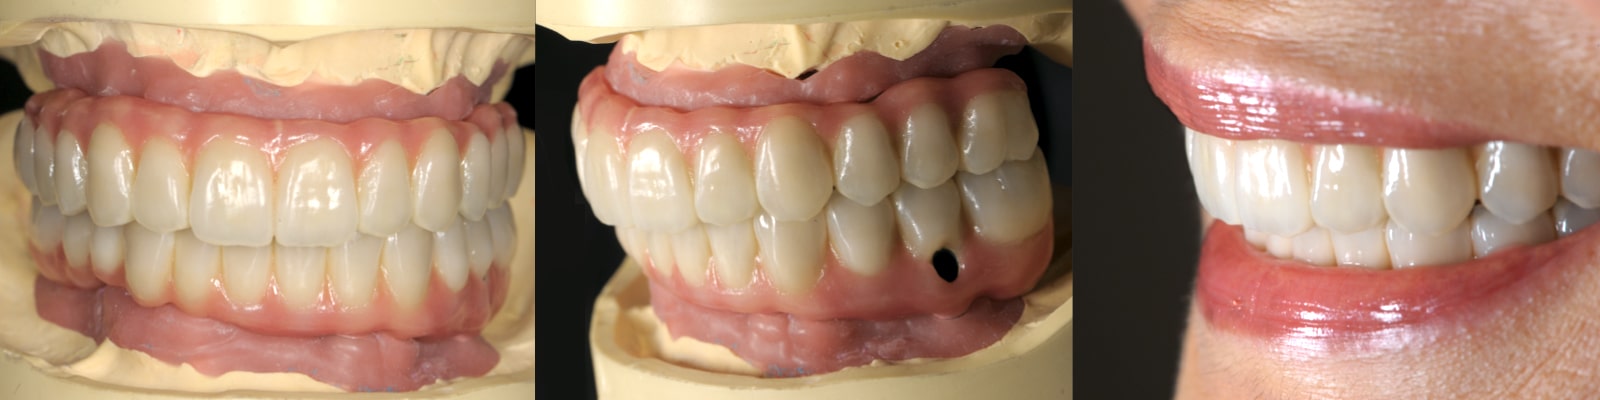

とびきり美しい上部構造

ただ治すのではなく、美しく治す。しかも、とびっきり美しく治すことにこだわっています。そのため、数々の賞を受賞する腕の良い歯科技工士と連携して歯をデザインしています。

短期間で劇的に見た目改善できる

しっかり何でも噛めるようになる

3Dスマイルデザイン、ワックスアップ、ラジオグラフィックガイド等によるプランニングに基づいて、患者様それぞれに合わせたオーダーメイドの治療を慎重に進めていきます。